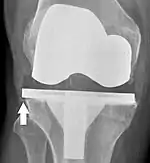

Loosening of the prosthesis can be indicated on X-ray by thin radiolucent spaces around the implant, or more obviously by implant displacement.[55]

Knee replacement is routinely evaluated by X-ray, including the following measures:

- FFC: frontal femoral component angle. It is typically regarded as optimal when being 2–7° in valgus.[62]

- FTC: frontal tibial component angle, which is regarded as optimal when being at a right angle. A varus position of more than 3° has generally been found to increase the failure rate of the prosthesis.[62]